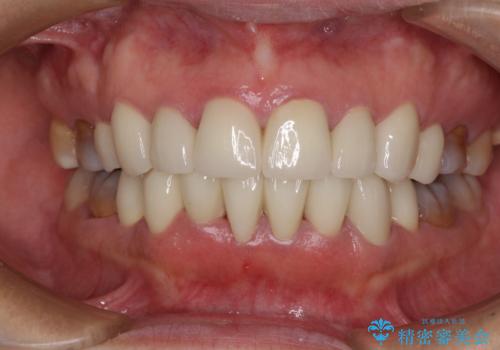

(3)上顎前歯12本おおび臼歯5歯

オールセラミック(ジルコニアクラウン)にて補綴

矯正歯科治療により、かみ合わせや歯並びを改善することができ、最も気にされていた歯の変色を自然な歯の色に仕上げることができ、大変満足していただけました。